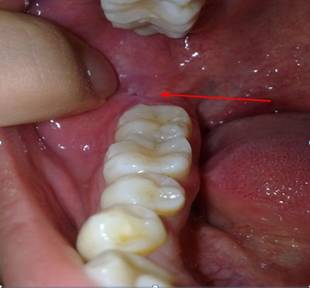

1.需要拔牙的情况,是智齿横向生长导致牙龈肿痛,这种情况要去医院检查、拍片后拔除。牙龈肿痛怎么办呢?